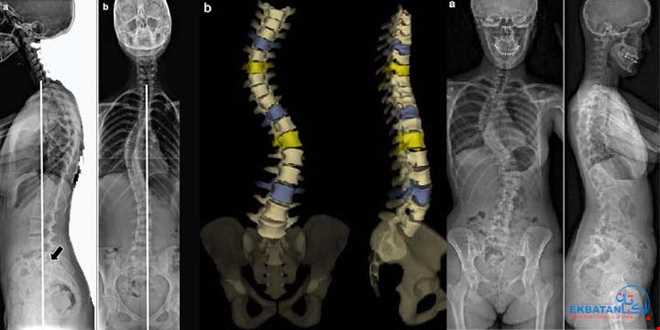

انحراف ستون فقرات (Scoliosis یا Kyphosis یا انحرافات ترکیبی) به حالتی گفته می‌شود که ستون مهره‌ها از خط طبیعی خود خارج شده و به شکل غیرعادی به طرفین یا جلو و عقب خم می‌شود. این وضعیت می‌تواند در هر سنی رخ دهد اما بیشتر در کودکان و نوجوانان، خصوصاً هنگام رشد سریع استخوان‌ها، دیده می‌شود.

1.    اسکولیوز (Scoliosis): انحراف جانبی ستون فقرات که ممکن است S یا C شکل باشد.

2.    کیفوز (Kyphosis): خمیدگی بیش از حد به سمت جلو، شایع‌تر در مهره‌های پشتی.

3.    لوردوز (Lordosis): افزایش قوس کمر به سمت جلو.

•    ارزیابی دقیق زاویه انحراف (زاویه کب) برای تصمیم‌گیری درمانی.